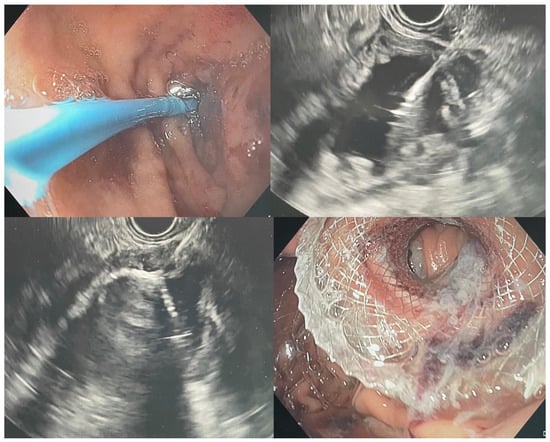

5.4. Endoscopic Gastroenterostomy

6.2. Gastroduodenal